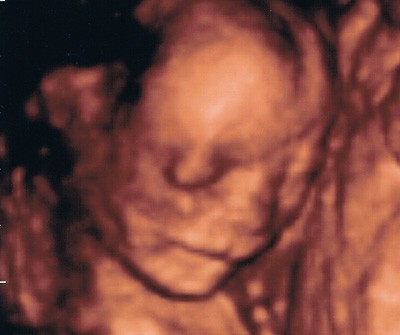

i okazało się ,że moja Dzidzia ma siusiaka!!